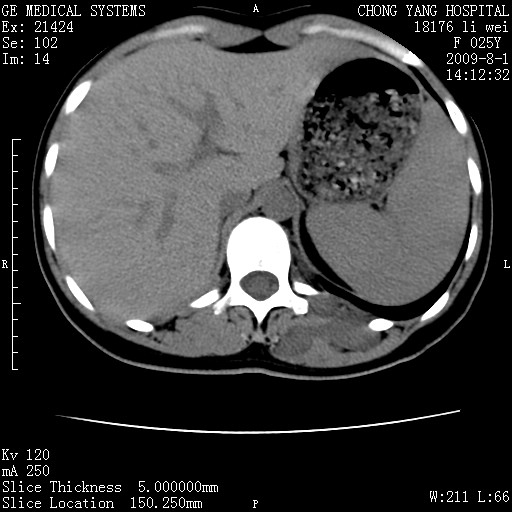

以下是引用pujunzhi在2009-8-1 20:23:00的发言:[br]胸椎旁及背部肌间良性病变,范围广,边界清,沿肌间生长,考虑淋巴管瘤、血管瘤,建议增强扫描。